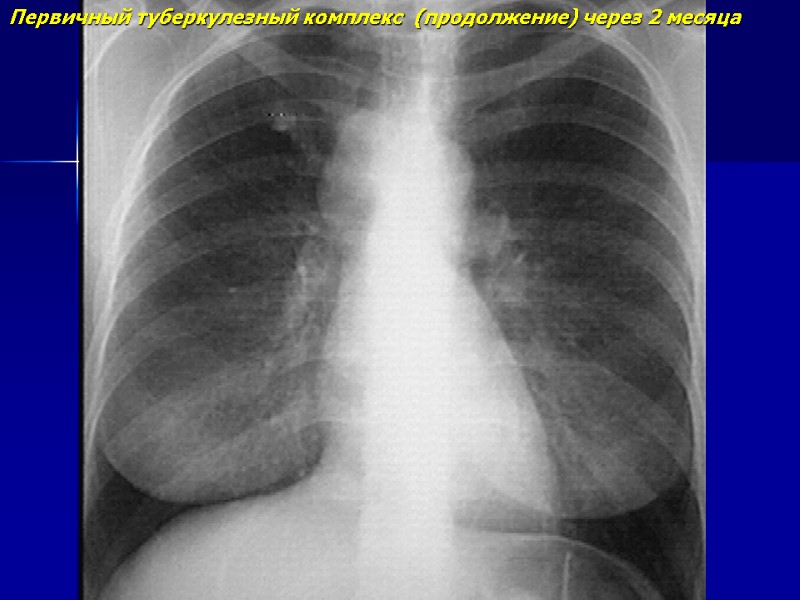

Первичный туберкулезный комплекс (продолжение) через 2 месяца